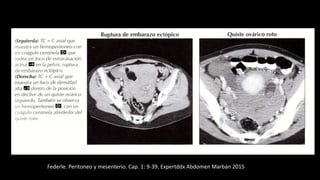

Hemoperitoneo

Federle. Peritoneo y mesenterio. Cap. 1: 9-39. Expertddx Abdomen Marbán 2015

Indicios útiles para diagnósticos

frecuentes de hemoperitoneo

En la TC se ve una gran masa pélvica de partes

blandas (M), de densidad heterogénea,que

empuja la vejiga (V) hacia delante. El

diagnóstico en esta paciente con una historia

de traumatismo fue hemoperitoneo.